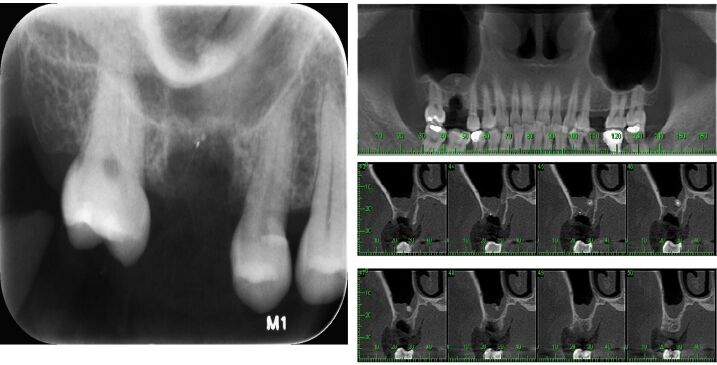

67.48歲男性三個月前拔除右上顎第一大臼齒,之後有黃鼻涕的問題產生,在X光及錐狀射束電腦斷層掃描 (cone-beam computed tomography, CBCT)檢查如附圖所示,此病變最可能的診斷為下列何者? (A)纖維性發育不良(fibrous dysplasia) (B)NK-T細胞淋巴瘤(NK-T cell lymphoma) (C)齒源性角化囊腫(odontogenic keratocyst) (D)殘根與鼻竇炎(retained root and sinusitis)